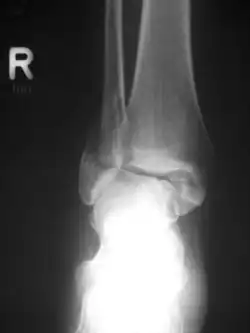

Eine Bimalleolarfraktur im seitlichen Röntgenbild … -

… und von vorne … -